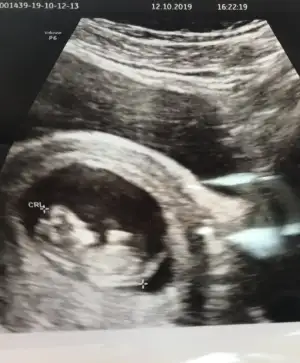

Erkek gibi ama 11 yada 12 hafta usg olmalıKızlar tahmini olan var mıı

saglıkla gelsin prensesIkra Meyra merhaba cinsiyeti öğrendik kızımız olacakmışBu da son ultrason fotoğrafımız 13 haftalık